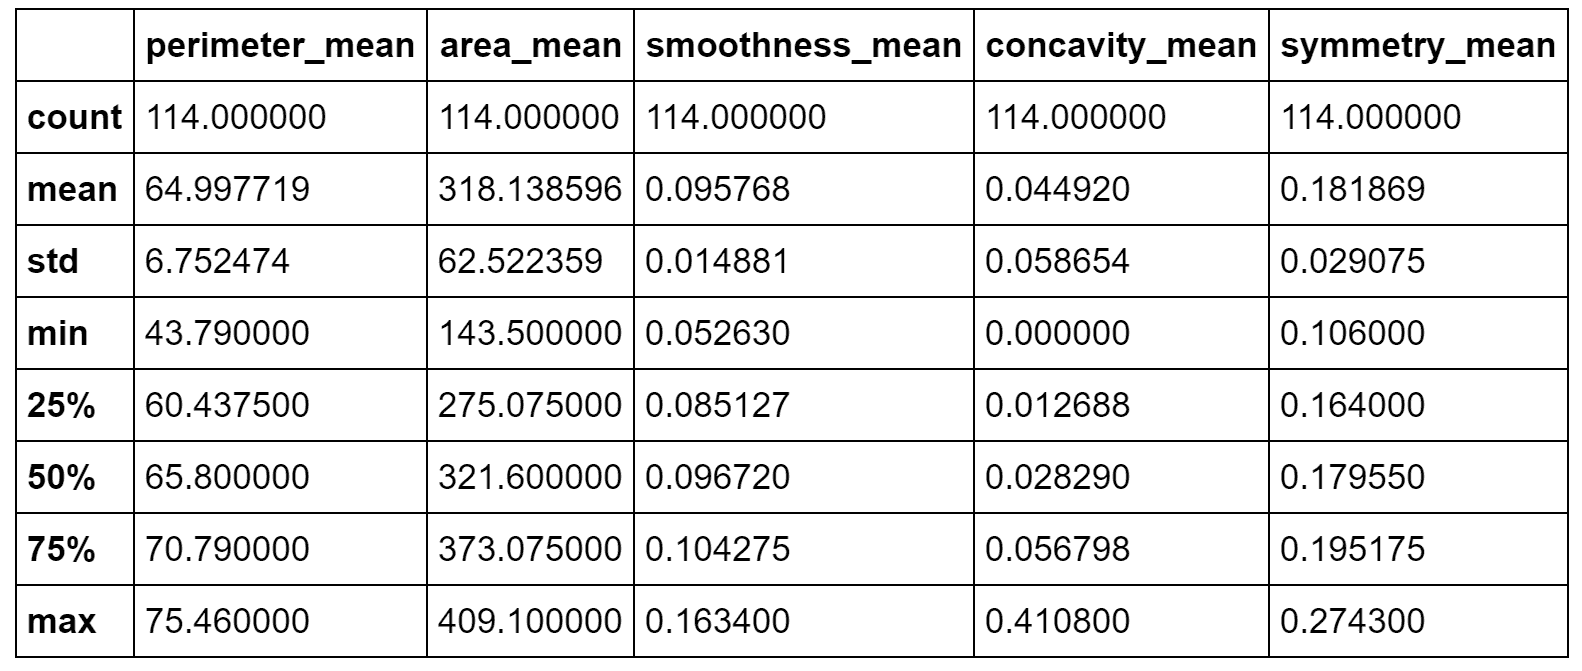

为了与良性样本进行比较,现在考虑由x > -10和20 < y < 50界定的区域如下:

sdff = dff[(dff.x > -10.0) & (dff.y > 20.0) & (dff.y < 50.0)]

print(sdff[['perimeter_mean', 'area_mean', 'smoothness_mean',

'concavity_mean', 'symmetry_mean']].describe())

结果显示在以下屏幕截图中:

良性群集的统计描述

在这种情况下,比 area_mean / perimeter_mean 约为4.89,但是area_mean具有较大的标准差(实际上,其最大值约为410)。 concavity_mean相对于前一个非常小(即使具有近似相同的标准差),而symmetry_mean几乎相等。 从这个简短的分析中,我们可以推断出symmetry_mean不是判别特征,而concavity_mean的比值area_mean / perimeter_mean小于5.42(考虑最大值)。 小于或等于0.04应当保证良性结果。 由于concavity_mean可以达到非常大的最大值(大于与恶性样本相关的最大值),因此有必要考虑其他特征,以便确定是否应将其值视为警报。 但是,我们可以得出结论,说属于这些群集的所有样本都是良性的,错误概率可以忽略不计。 我想重复一遍,这不是真正的分析,而是更多的练习,在这种情况下,数据科学家的主要任务是收集可以支持结论的上下文信息。 即使存在基本事实,该验证过程也始终是强制性的,因为根本原因的复杂性可能导致完全错误的陈述和规则。